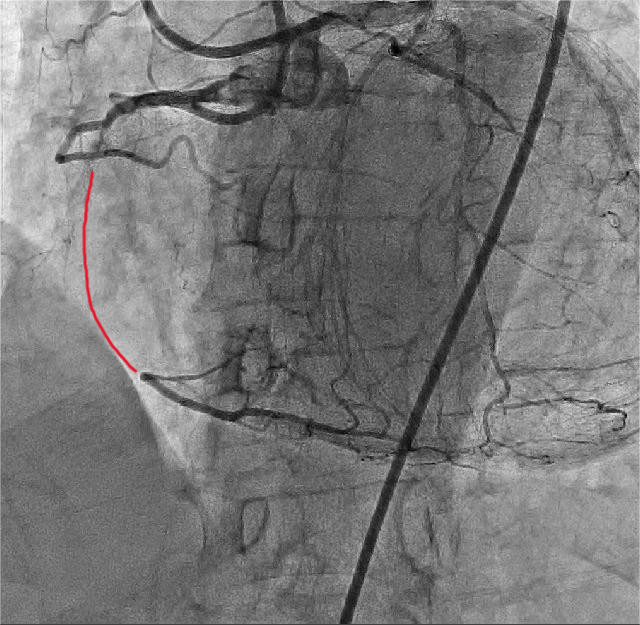

4月19日,手术团队对该患者开展冠状动脉造影检查。造影结果提示:右冠状动脉中段闭塞病变,前后降和回旋支开口狭窄50%,前降支动脉通过新生血管向右冠状动脉形成侧枝血供。朱舜明副主任医师向患者和家属告知病情严重性,为保证手术安全,建议其择期行逆向冠脉病变治疗术或保守治疗。两难抉择下,患者家属仍考虑择期采用新技术开通闭塞血管。手术团队再次分析患者病情并制定详细方案:拟择期采用Reverse-CART通过前降支侧枝血管逆行开通闭塞右冠状动脉。

4月24日,朱舜明副主任医师为患者制定周密的手术方案和风险处理方案,朱舜明副主任医师、唐治国主治医师、张翔主治医师、张豪住院医师开展持续3小时的介入手术。术中穿刺桡动脉和股动脉,双路径同时造影显示病变血管完整结构,开展Reverse-CART技术,将逆向导丝送入正向指引导管,跟进微导管,交换导丝后用球囊扩张病变,沿逆向导丝送入双腔微导管至闭塞血管远端,沿双腔微导管送入正向工作导丝至右冠后降支,并退出逆向微导管和导丝,采用血管内超声精细评估病变情况,最终向右冠状动脉内植入3枚支架。术后多体位造影未见残余狭窄及贴壁不良,完美结束手术。

图1 股动脉和桡动脉双路径造影提示:右冠状动脉中段闭塞病变,红色线条:闭塞血管段。